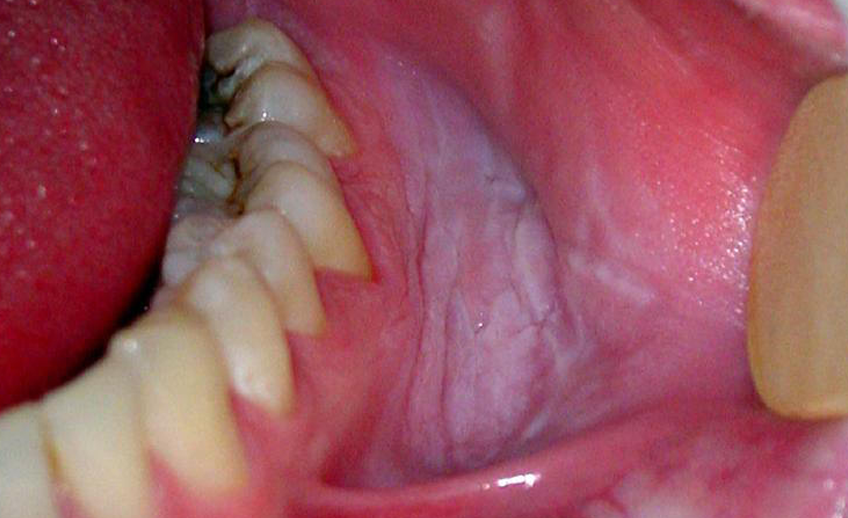

RESTRICTED MOUTH OPENING ( OSMF)

Limited mouth opening (LMO) in oral submucous fibrosis (OSF) ..

RED AND WHITE LESIONS OF THE ORAL CAVITY

Generally the red and white lesions are benign and a...